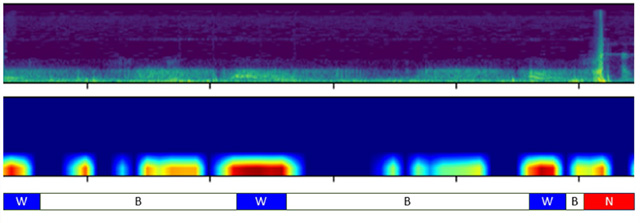

• AST 모델이 천명음(W)에는 강하게 반응하지만, 정상호흡(B)과 소음(N)에는 미미하게 반응하고 있다. /이미지 제공=분당서울대병원

▲ AST 모델이 천명음(W)에는 강하게 반응하지만, 정상호흡(B)과 소음(N)에는 미미하게 반응하고 있다. /이미지 제공=분당서울대병원

AST 모델은 호흡음을 멜 스펙트로그램(Mel Spectrogram) 형태로 변환한 후, 이를 16×16 크기의 조각 단위로 나누어 각 조각 간의 관계를 학습하도록 설계되었다. 이 방식은 전체적인 문맥 정보를 고려할 수 있어, 부분 정보에만 의존하는 기존 CNN 방식보다 정밀한 분류가 가능하다.

분류 성능을 평가한 결과, AST 모델은 정확도 91.1%, 정밀도 88.2%, F1-Score 82.1%를 기록하며 CNN 모델(정확도 83.6%, F1-Score 65.7%)보다 우수한 성능을 보였다. 특히 AST는 정상 호흡음이나 소음에는 낮은 반응을 보이며 천명음에만 선택적으로 반응하는 특징도 나타났다.